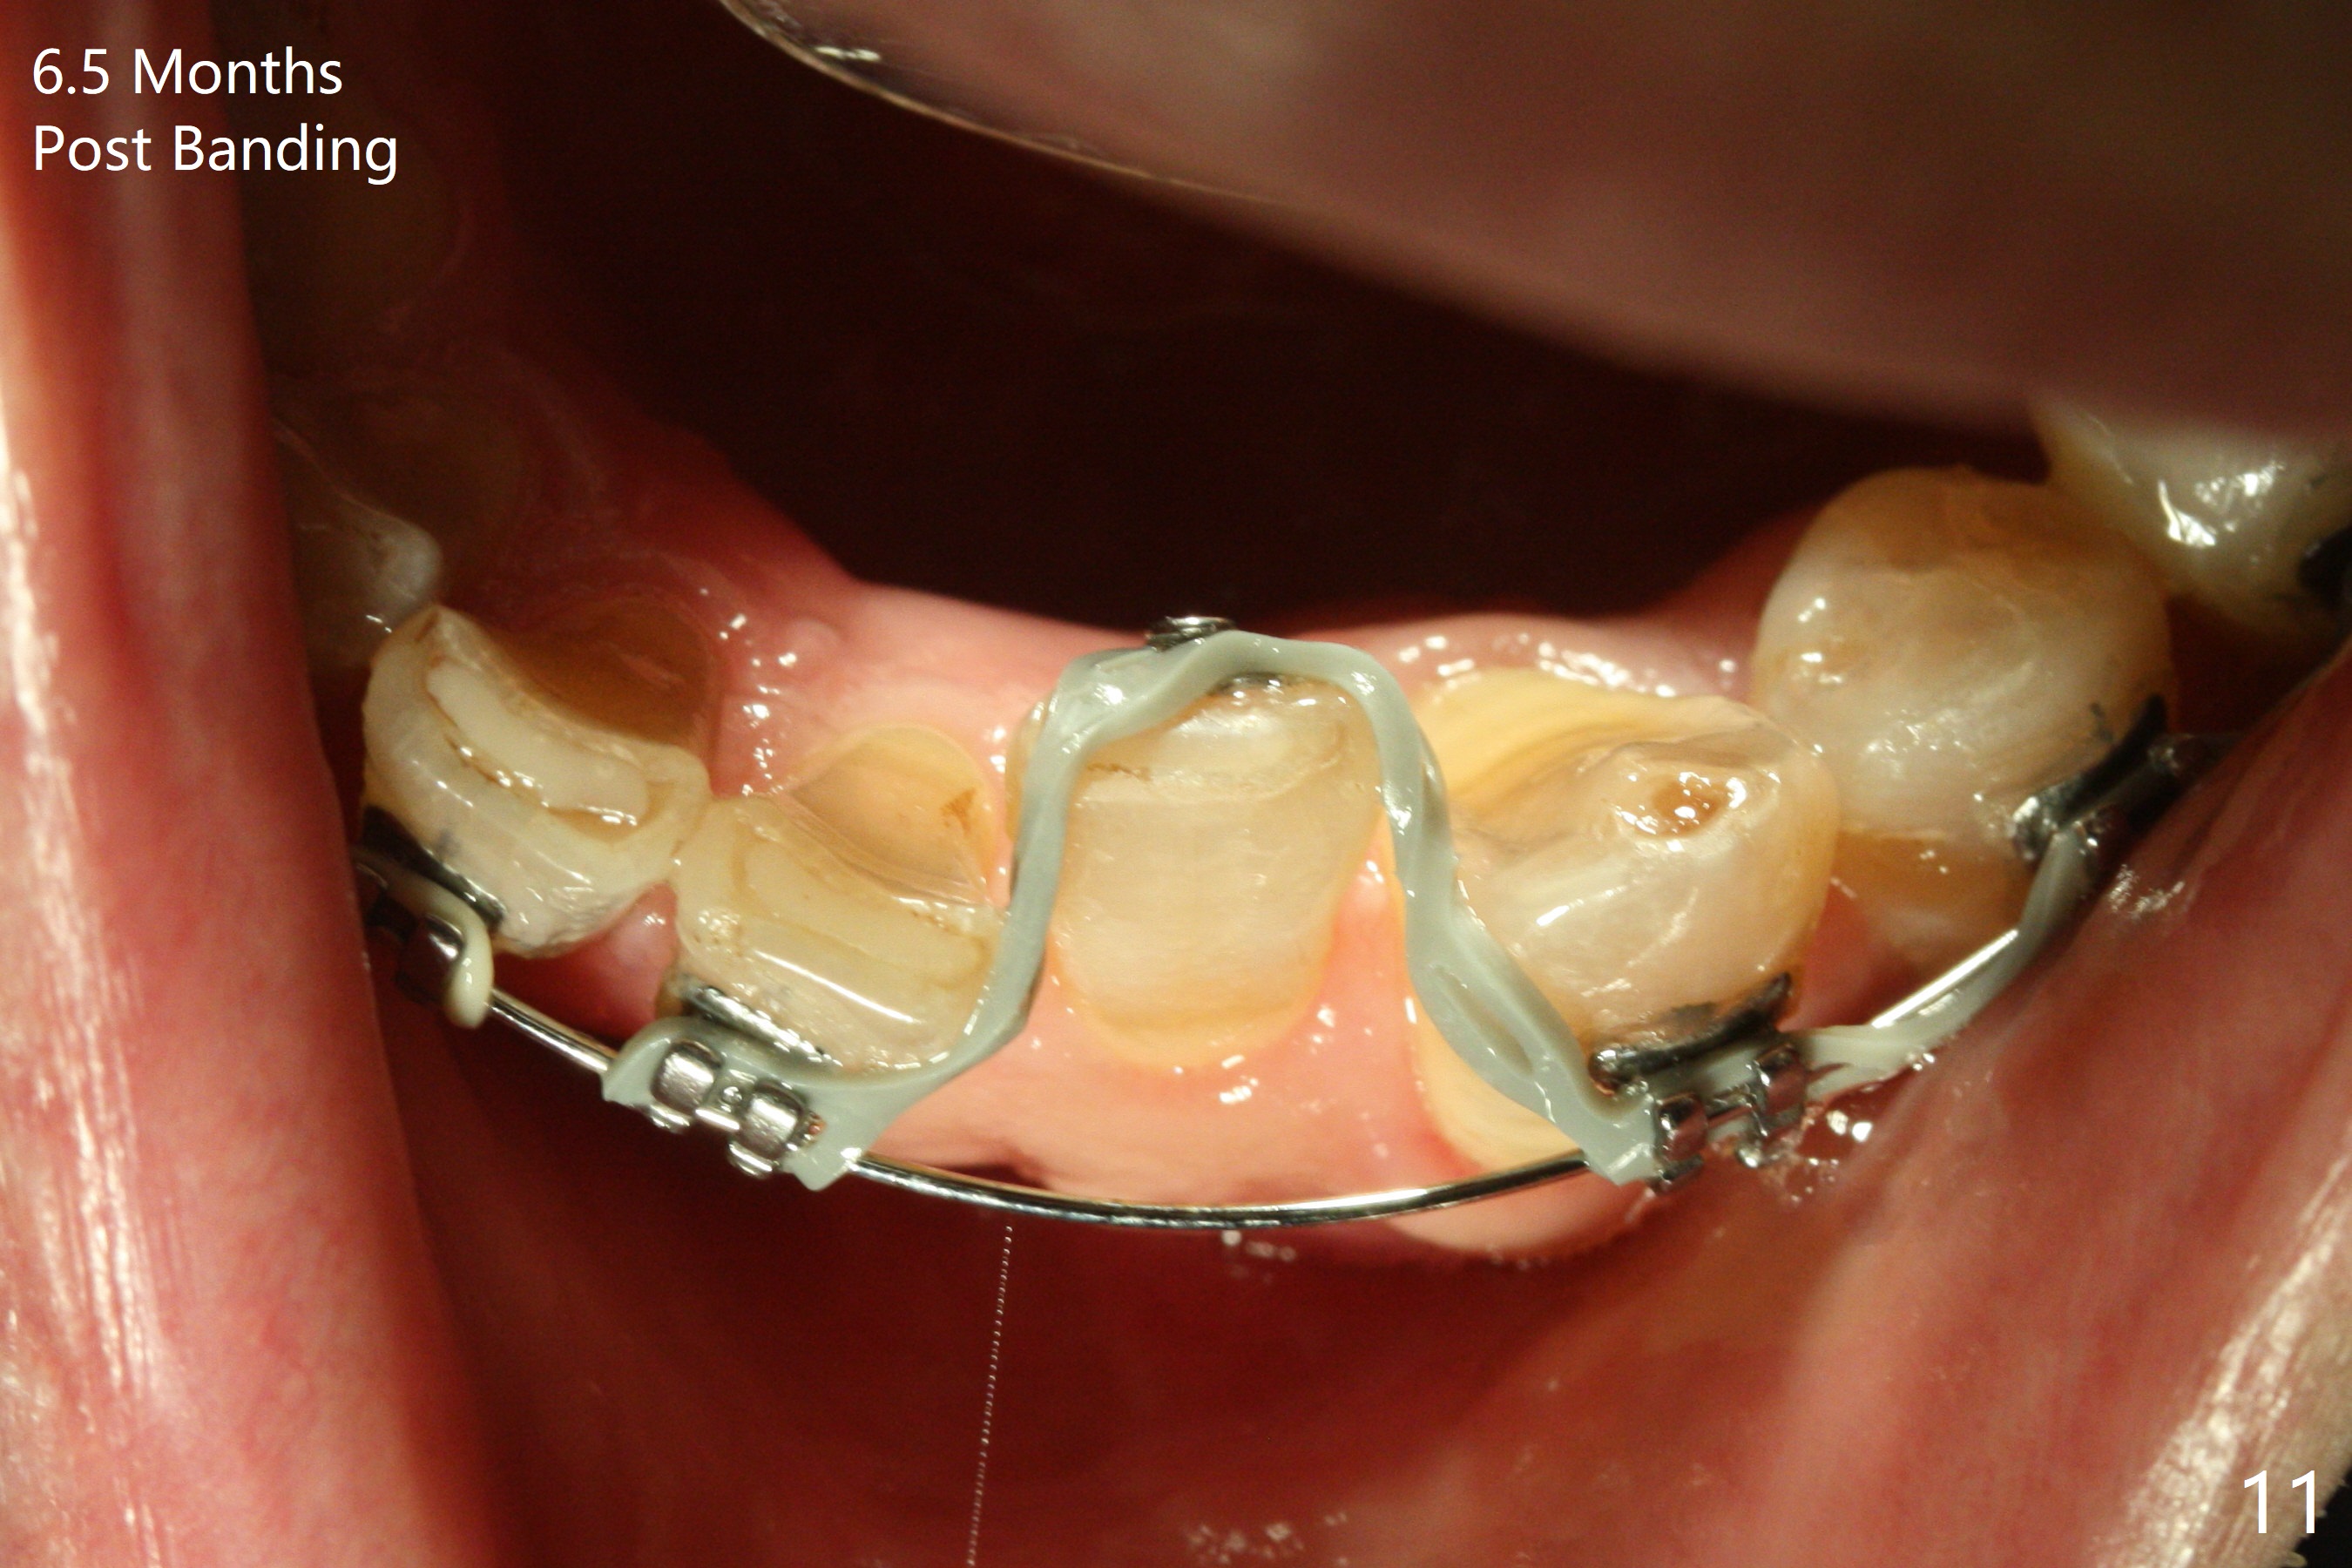

Two weeks post provisionalization over implants at #18 and 19 (4.5 months postop), acrylic is added to the provisional (Fig.1 *) and composite is placed on the other side (Fig.2 *) for clearance (Fig.3). Six days post bracketing, the diastema between LL5 and 6 decreases (Fig.4 between arrows, as compared to Fig.3), suggesting uprighting and distalization of the affected tooth. The diastema increases by trimming the mesial surface of LL6 provisional (Fig.5 *) prior to power chain placement. More acrylic is added to the occlusal surface of LL 6 and 7; more composite to that of UR3 (as compared to Fig.2) for clearance. Power chains change every week. LL5 is uprighted and distalized 1.5 months post banding (Fig.6,7 (14 niti)). Anterior brackets will be placed to correct LL2 cross bite next visit. Three weeks post open coil spring (5 months post initial banding), there is a space between LL2 and 3 (Fig.8) and between LL3/4 (Fig.9). The latter reduces instantly post power chain between LL3 and 6 (Fig.10). There is enough space for LL2 and sling shot is used to correct the cross bite 6.5 months post initial banding (Fig.11). The cross bite is corrected in 1.5 months after occlusal clearance is established (Fig.12). The lower left alignment is within normal limit, although in cross bite with the opposing dentition, immediate post molar crown cementation (Fig.13).